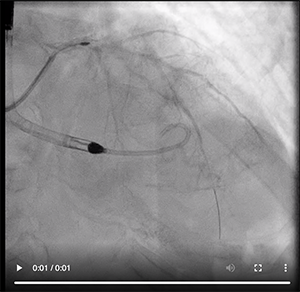

To reduce the risk of extensive stenting, the revascularization procedure would target only the LM bifurcation, while a conservative strategy was chosen for the marginal branch ostial lesion, which we believed would not further impact the patient’s prognosis. Considering the low LVEF as well as the complexity of the LM bifurcation, including the possibility of rotablator debulking of this lesion, left ventricular support was considered appropriate. An Impella CP device (Abiomed, Inc.) was implanted after careful angiographic evaluation of the right femoral and iliac arteries (Video 2).

Video 4. Stent positioning.

The LM-LAD lesion was then crossed with a 1.5-mm rotablator burr at 140,000 rpm. There were no major visual dissections after rotablator debulking (Video 3). Both lesions were rewired, and a V-stent technique was used (simultaneous ostial stenting of the ostial LAD and left circumflex arteries) (Video 4 and Video 5A, Video 5B). The main reason for this choice was the very short LM, which made any other technique nearly impossible. The inability to readdress a possible left circumflex pinching after LM-LAD provisional stenting was another reason that a V-stent technique was chosen.